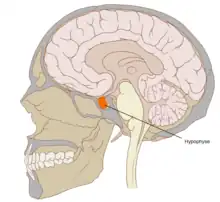

Hypophyse

L'hypophyse (du grec ancien : ὑποφύσις / hupophúsis, « naissance ou croissance en dessous »[1]) ou glande pituitaire est une glande endocrine qui secrète de nombreuses hormones[2].

L'hypophyse se trouve dans une cavité osseuse, la fosse hypophysaire qui se situe dans l'os sphénoïde. Elle est protégée par la selle turcique. Elle est reliée à une autre partie du cerveau appelée l'hypothalamus par une tige hypophysaire (également appelée tige pituitaire). Elle produit des hormones qui gèrent une large gamme de fonctions corporelles, dont les hormones trophiques qui stimulent les autres glandes endocrines. Cette fonction lui a valu de se faire appeler par les scientifiques « glande maîtresse » du corps, mais aujourd'hui on sait que l'hypophyse est régulée par les hormones (neuro-hormones) émises par l'hypothalamus.

Chez l'être humain l'hypophyse mesure environ 10 millimètres de diamètre et pèse environ 0,5 gramme[3].